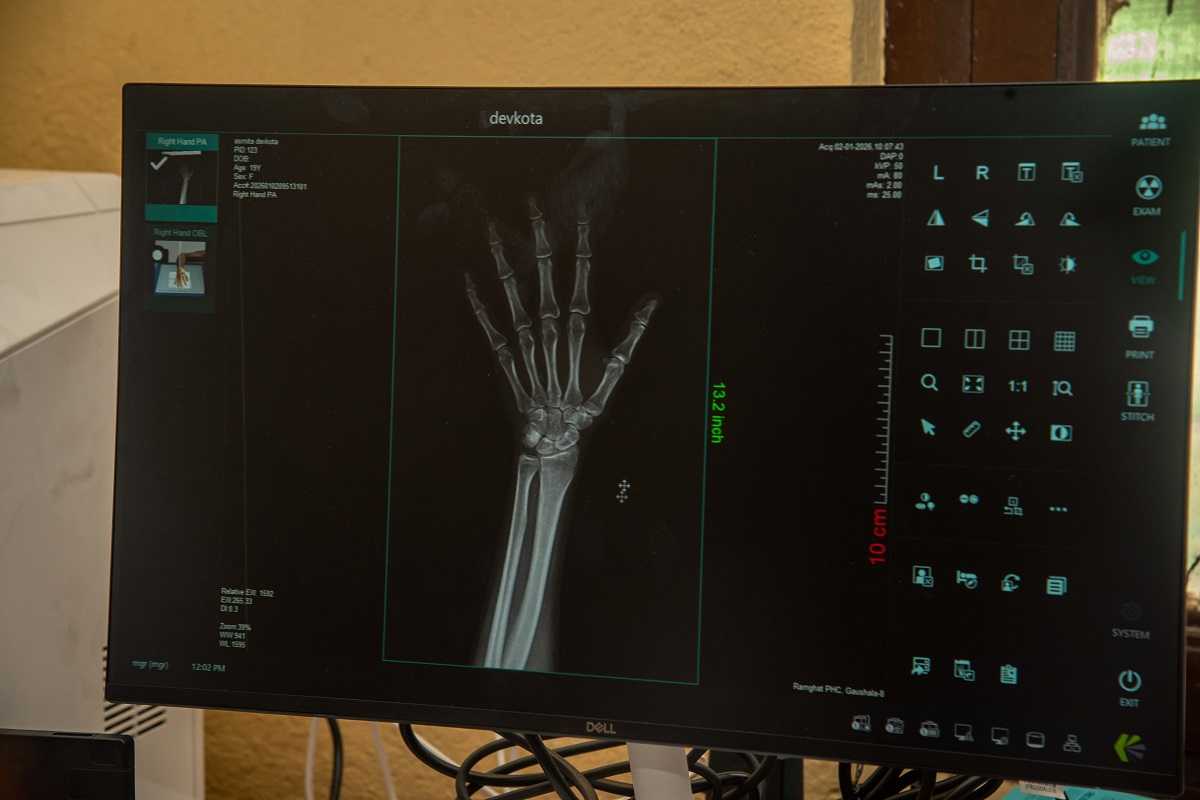

काठमाडौँ । काठमाडौँ महानगरपालिकाको वडा नम्बर ८ मा आजदेखि एक्स–रे सेवा प्रारम्भ भएको छ । जयबागेश्वरीस्थित वडा कार्यालय परिसरमा स्थापना गरिएको एक्स-रे कक्षको उद्घाटन गर्दै महानगरपालिकाका उपप्रमुख सुनिता डंगोल र वडाध्यक्ष एवं महानगरपालिकाको सम्पदा तथा पर्यटन समितिका संयोजक आशामान संगतले संयुक्त रुपमा सेवा प्रारम्भ गर्नुभएको हो । कक्षमा करिब ३२ लाख रुपियाँ लागतमा खरिद गरिएको अत्याधुनिक मेसिन छ ।

रामघाट प्राथमिक स्वास्थ्य केन्द्रअन्तर्गत ३ जना मेडिकल अधिकृतबाट सेवा प्रवाह भइरहेको जानकारी दिँदै स्वास्थ्य विभागका प्रमुख दिपककुमार के. सी. ले भन्नुभयो, ‘एक्से-रे सेवा हरेक दिन सञ्चालन हुनेछ भने भिडियो एक्स-रे सेवा हरेक शुक्रबार सञ्चालन हुनेछ ।’

विभागको भण्डार (स्टोर) शाखा प्रमुख कमलप्रसाद भट्टराईका अनुसार वडा नम्बर ७, ८, १०, १२, १४, १६, १९, २६, २७ र ३२ गरी १० वटा वडामा एक्स-रे सेवा जडान हुँदैछ । यसका लागि १० जना रेडियोग्राफर नियुक्त गरिसकिएको छ ।